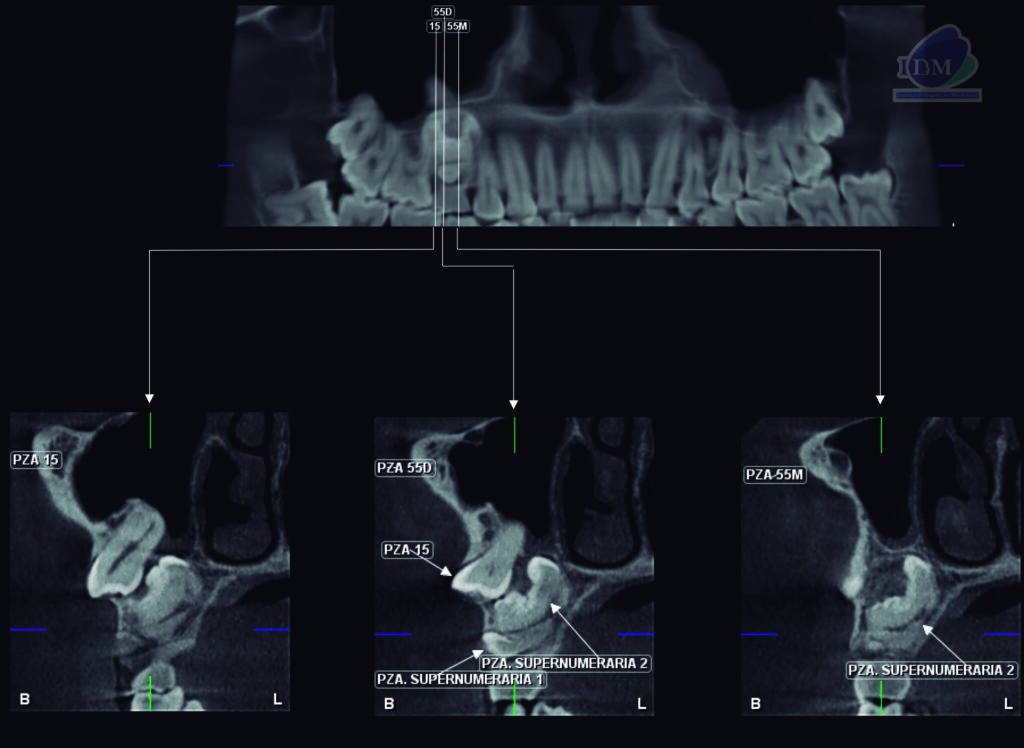

A la evaluación de la tomografía volumétrica (CBCT) en los cortes axiales (Figura 2) y transaxiales (Figura 3), se aprecia pieza supernumeraria 1 localizada entre pieza 55 y pieza supernumeraria 2. Imagen hiperdensa (pieza supernumeraria 2), de limites definidos y forma irregular, que se extiende en sentido cefálico caudal desde piso de seno maxilar hasta pieza supernumeraria 1, que ocasiona el desplazamiento de pieza 15 comprometiendo piso de seno maxilar.

CORTES TRANSAXIALES